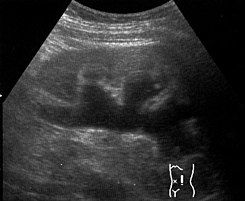

Ultrasonido Renal

El ultrasonido renal es un estudio que nos permite valorar ambos riñones, y detectar en el si existen lesiones, o alguna patologia derivada de litos o masas en su interior, o su parenquima.